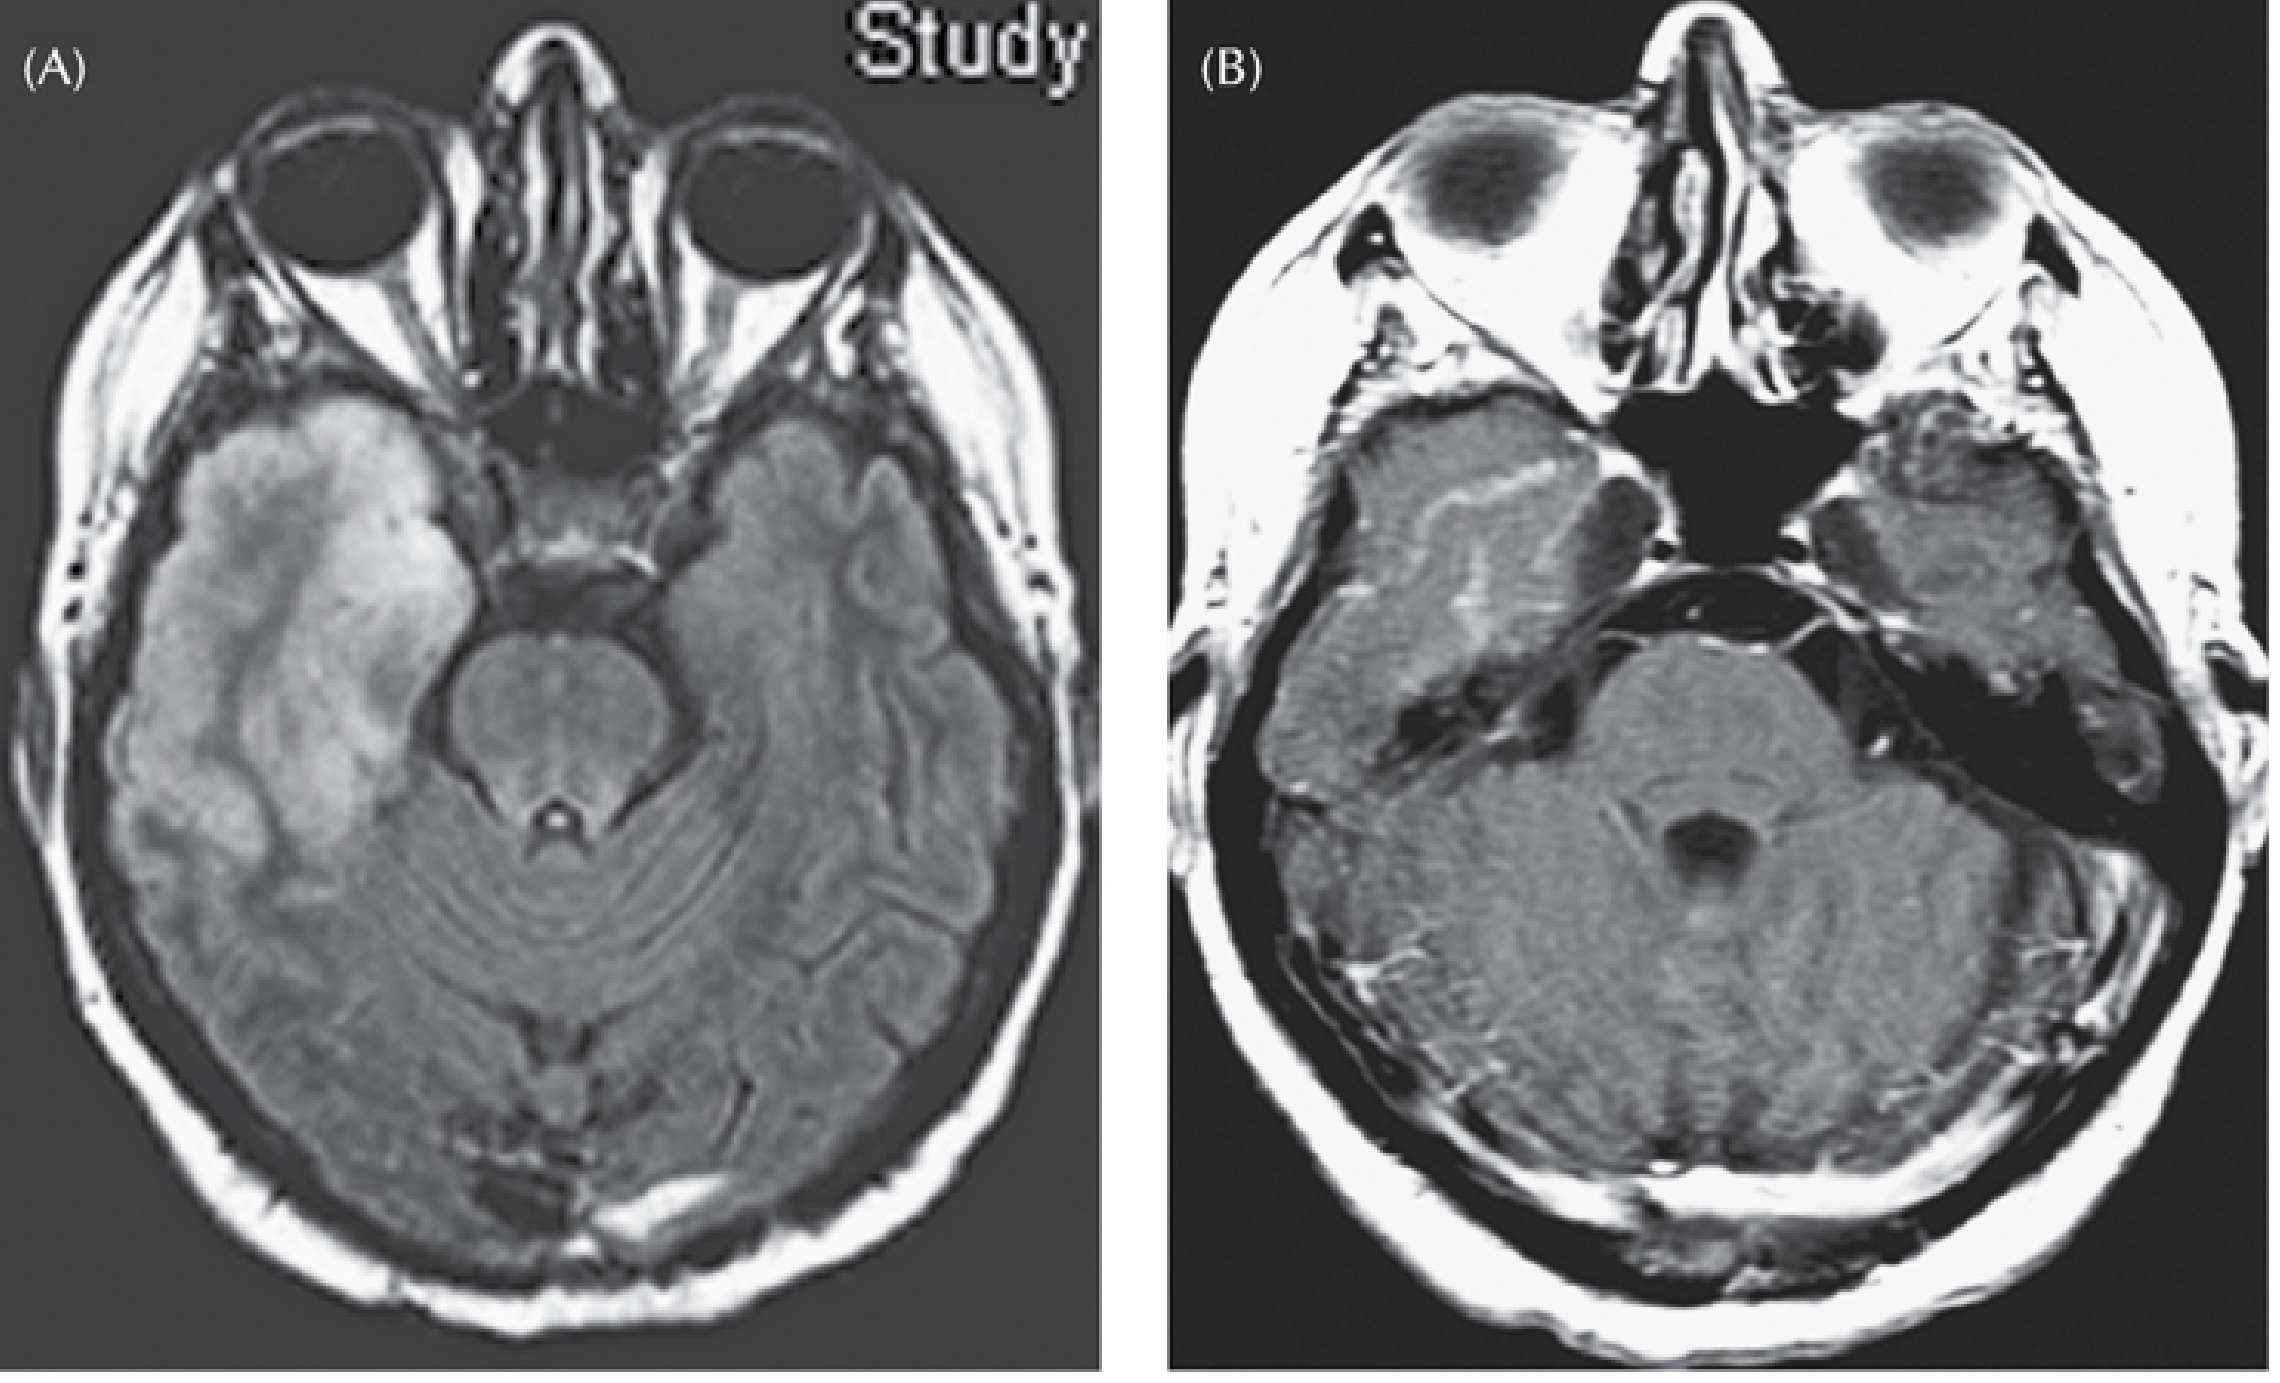

| FLAIR / T2 | High signal + cortical swelling in anteromedial temporal lobe, insula, cingulate β earliest and most sensitive; abnormal within 2 days |

Abnormalities start unilaterally but frequently spread to the contralateral temporal lobe. Bilateral involvement on MRI is a poor prognostic sign.

| MRI hallmark | Temporal T2/FLAIR swelling | Diffuse WM T2, atrophy | Meningeal enhancement; infarcts | DWI cortical ribboning | Basilar enhancement; hydrocephalus |